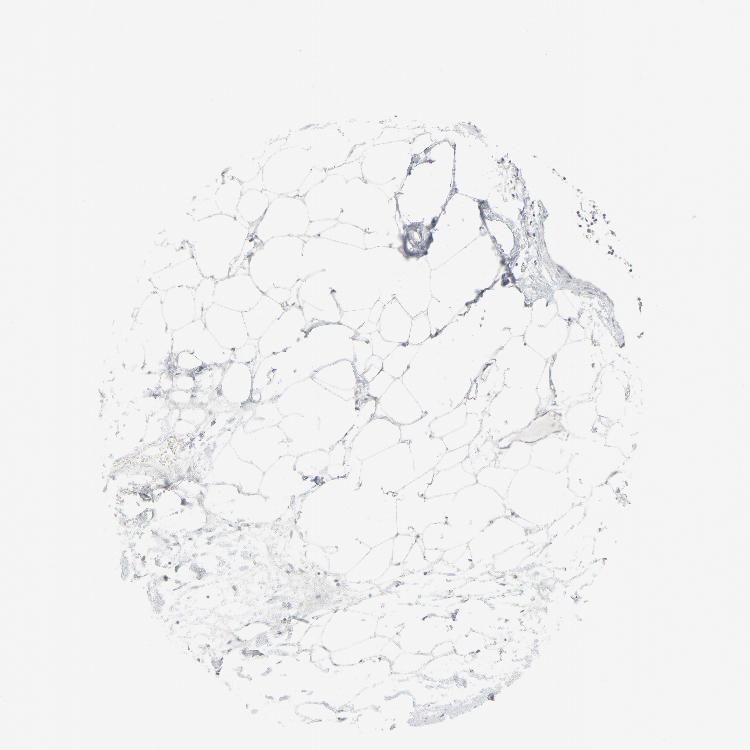

ADIPOSE TISSUE - Antibody stainingi

Antibody staining in the annotated cell types in the current human tissue is reported as not detected, low, medium, or high, based on conventional immunohistochemistry profiling in selected tissues. This score is based on the combination of the staining intensity and fraction of stained cells.

Each image is clickable and will lead to virtual microscopy that enables deeper exploration of all samples and also displays staining intensity scores, fraction scores and subcellular localization as well as patient and tissue information for each sample.

Antibody HPA003278Antibody CAB022450

Adipocytes Not detectedNot detected